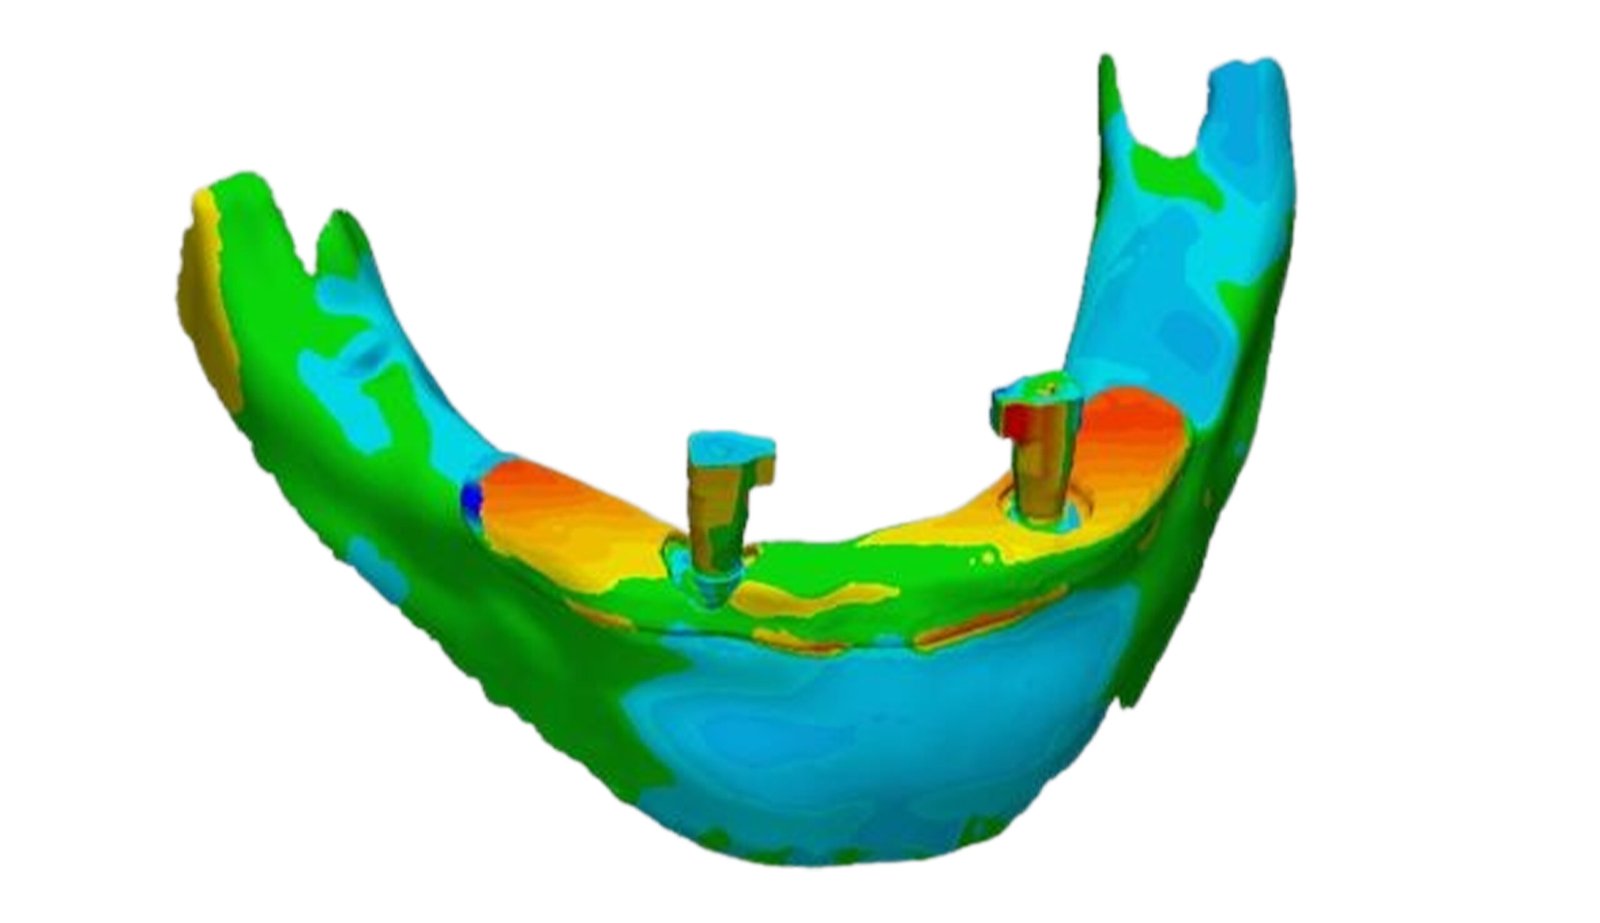

This section specializes in high-precision 3D deviation mapping to compare pre- and post-treatment anatomical or implant-related geometries. Using advanced superimposition and deviation algorithms, we quantify micro-level shifts, deformation zones, and structural discrepancies with sub-millimeter accuracy. These analyses support quality control, surgical verification, and design validation. The resulting deviation heat-maps provide clear, data-driven insights that enhance clinical decision-making and device optimization.